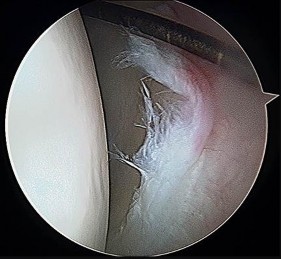

Which image seen during arthroscopic treatment is most likely associated with this patient’s condition?

An otherwise healthy 31-year-old man has had right knee pain for the past 9 months. His former physician

administered a cortisone injection and ordered 6 months of physical therapy. The patient later had an arthroscopy with debridement of the right knee by another physician and completed another course of physical therapy. The patient received minimal relief from these treatments and still is not able to walk longer distances or go on hikes. On examination, he is a healthy appearing male with a body mass index of 24 kg/m2. He has a small effusion, minimal quadriceps atrophy, no tenderness about the knee, full range of motion, stable to varus and valgus stress at 30° of flexion, a grade 1 Lachman test, and a normal posterior drawer. Figures 1 through 4 are his arthroscopic views, radiograph and MRI scan from his prior surgical procedure. What is the next most appropriate step in treatment?